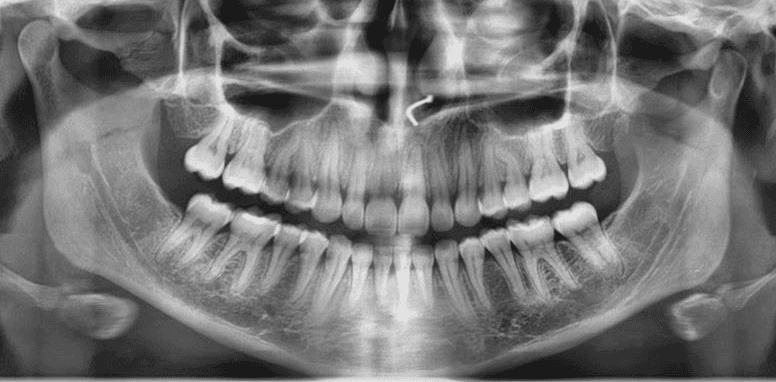

Final results

X-RAYS